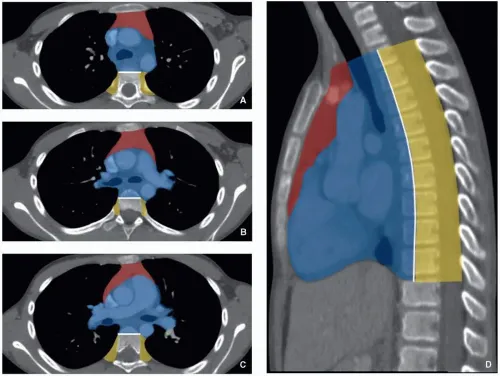

Mediastinum: Central thorax. Classifications: Felson (CXR), ITMIG/IASLC (CT).

ITMIG Classification (CT-based): Prevascular, Visceral, Paravertebral compartments.